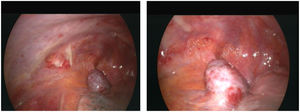

To confirm the cause of the mediastinal lesion, the patient underwent medical thoracoscopy. A hypervascular, sessile mass was observed in the prevascular mediastinum and subsequently biopsied (Fig. 2). The tumour was not separated from the aorta during the procedure. Histological examination of pleural fragments showed vascular congestion, alveoli filled with macrophages, and compression of the alveoli by a fibroadipose tissue 'mass' (MDM2-) and smooth muscle (actin+), accompanied by capillary proliferation (CD34+). Thrombi were frequently present. No necrosis or mitoses were detected. Histochemical investigation for microorganisms, including PAS, Ziehl-Neelsen, and Grocott staining, yielded negative results. Immunohistochemical analysis was performed to explore other neoplasms, and results for calretinin, BER-EP4, S100, CD1a, Melan-A, HMB45, and p53 were negative (Fig. 3)